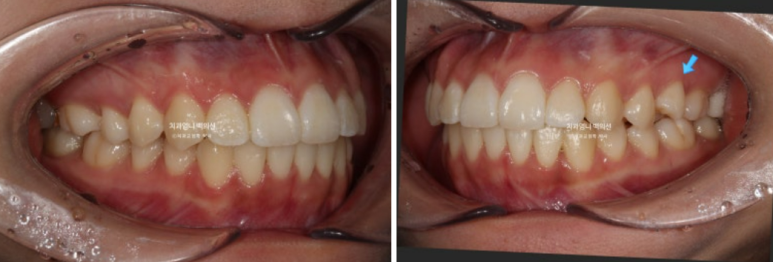

23.12~24.09

고무줄 사용으로 송곳니 교합관계도 개선이 되었습니다.